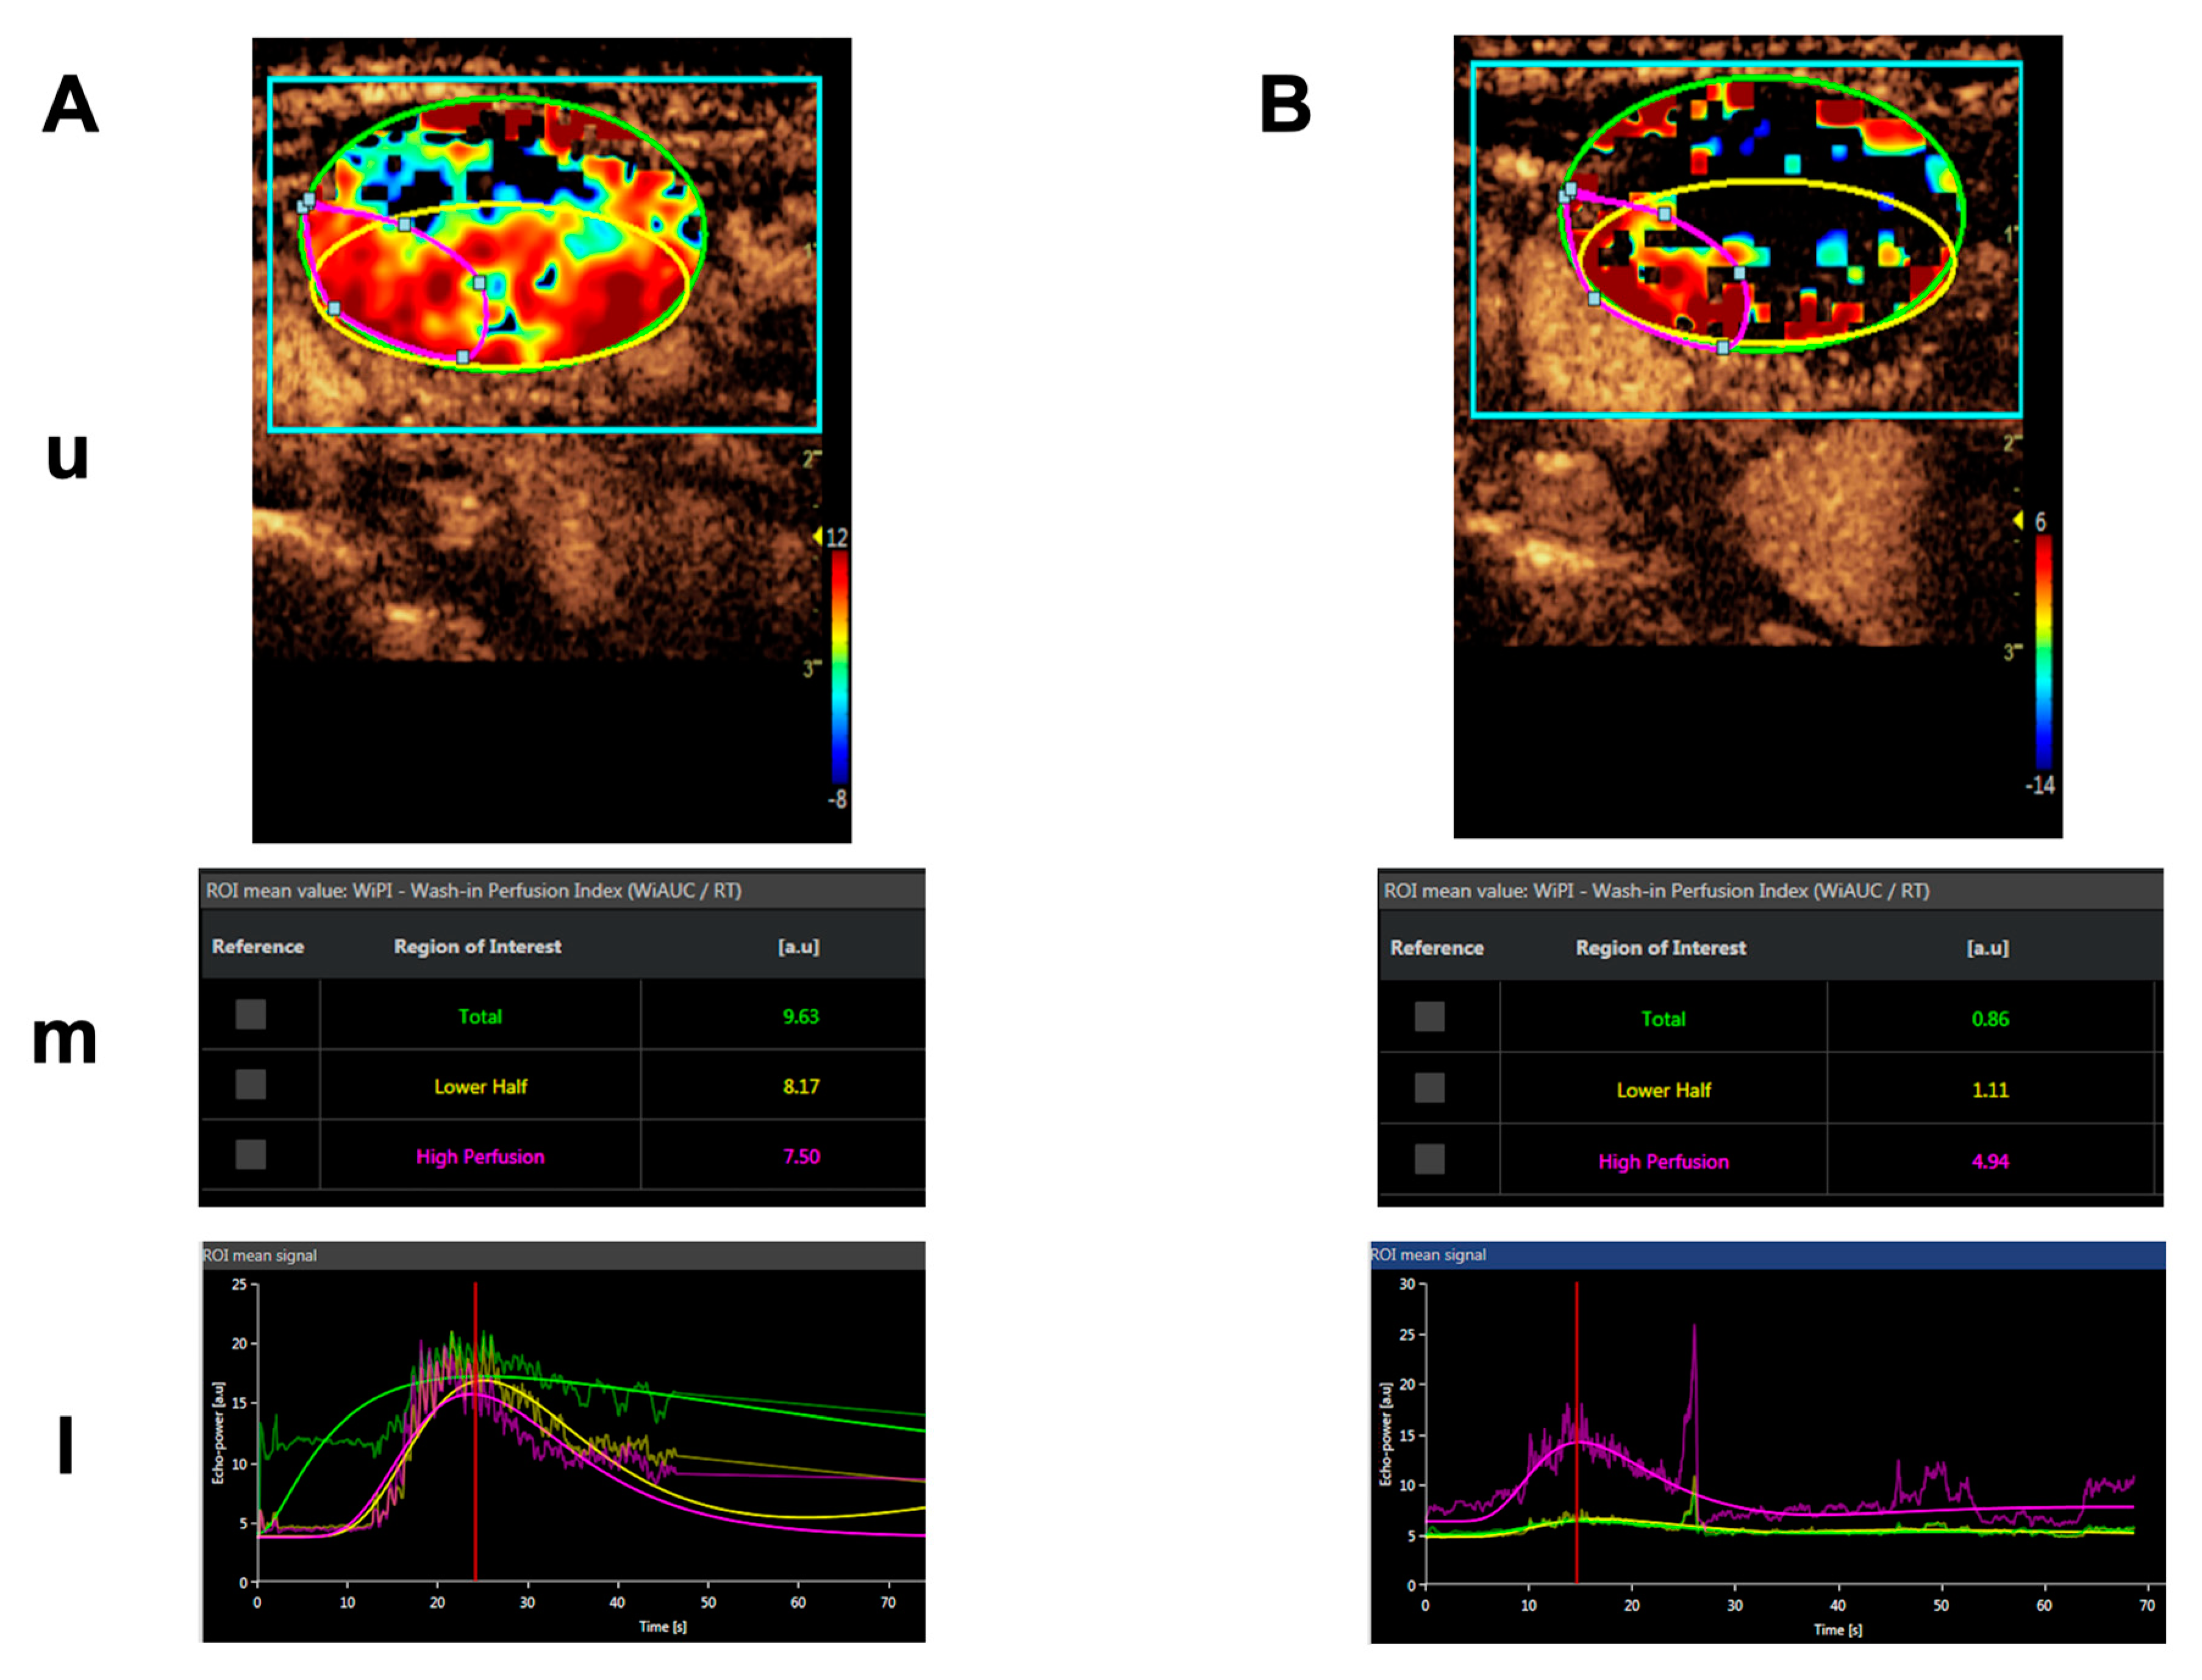

Importantly, blood flow was significantly and specifically reduced in the tumor tissue of all measurable lesions as shown by dynamic contrast-enhanced ultrasound (CEUS) and dynamic contrast-enhanced (DCE) magnetic resonance imaging (MRI), serving as evidence for the mechanism of action of tTF-NGR. An example of a CEUS imaging series in one patient is shown in Figure 4. Induced by therapy with tTF-NGR, contrast flow through the vasculature of the metastatic lesion decreased by more than 1-log step in the total lesion. However, the blood flow reduction was less pronounced in a “high perfusion” area and in parts of the rim of the lesion. Normal liver tissue did not show this blood flow decrease. Following tTF-NGR application some tumor lesions developed intratumoral hemorrhage and necrosis, although no definitive treatment response was reached according to the Response Evaluation Criteria in Solid Tumors (RECIST). At 8 to 9 h the terminal half-life of tTF-NGR was reached without accumulation following daily infusions. In summary, the single-agent treatment regimen with tTF-NGR was proven to be safe for administration, and imaging correlation of significant reduction of blood flow in tumor lesions served as evidence for the mechanism of action.

Figure 4.

Contrast-enhanced ultrasound (CEUS) imaging series of a lymphnode metastasis of a medullary thyroid carcinoma. (A). Shortly before treatment. (B). After 5 days of daily treatment with 4 mg/m2 bsa tTF-NGR. Upper panels for (A,B) (u): Heat maps of dynamic CEUS. Color scales at the right lower corner of each photograph semiquantify contrast perfusion (red = high, blue/black = low). The green circles represent “regions of interest” (ROI) for the “total” lesion, the yellow circles represent the “lower half” of the lesion, and the red circles represent a “high perfusion” area of the lesion. Middle panels for (A,B) (m): CEUS arbitrary units (a.u.) for the wash-in perfusion index (WIAUC/RT; for the methodological details see [88]) representing the contrast flow through the vasculature of the lesion. For color representation of the 3 different ROI measured, see upper panel. Lower panels for (A,B) (l): Graphic follow-up of the wash-in perfusion index representing the contrast flow through the vasculature of the lesion for 70 sec starting with the injection of contrast via peak-enhancement until wash-out. For color representation of the 3 different “regions of interest” (ROI) see upper and middle panels.